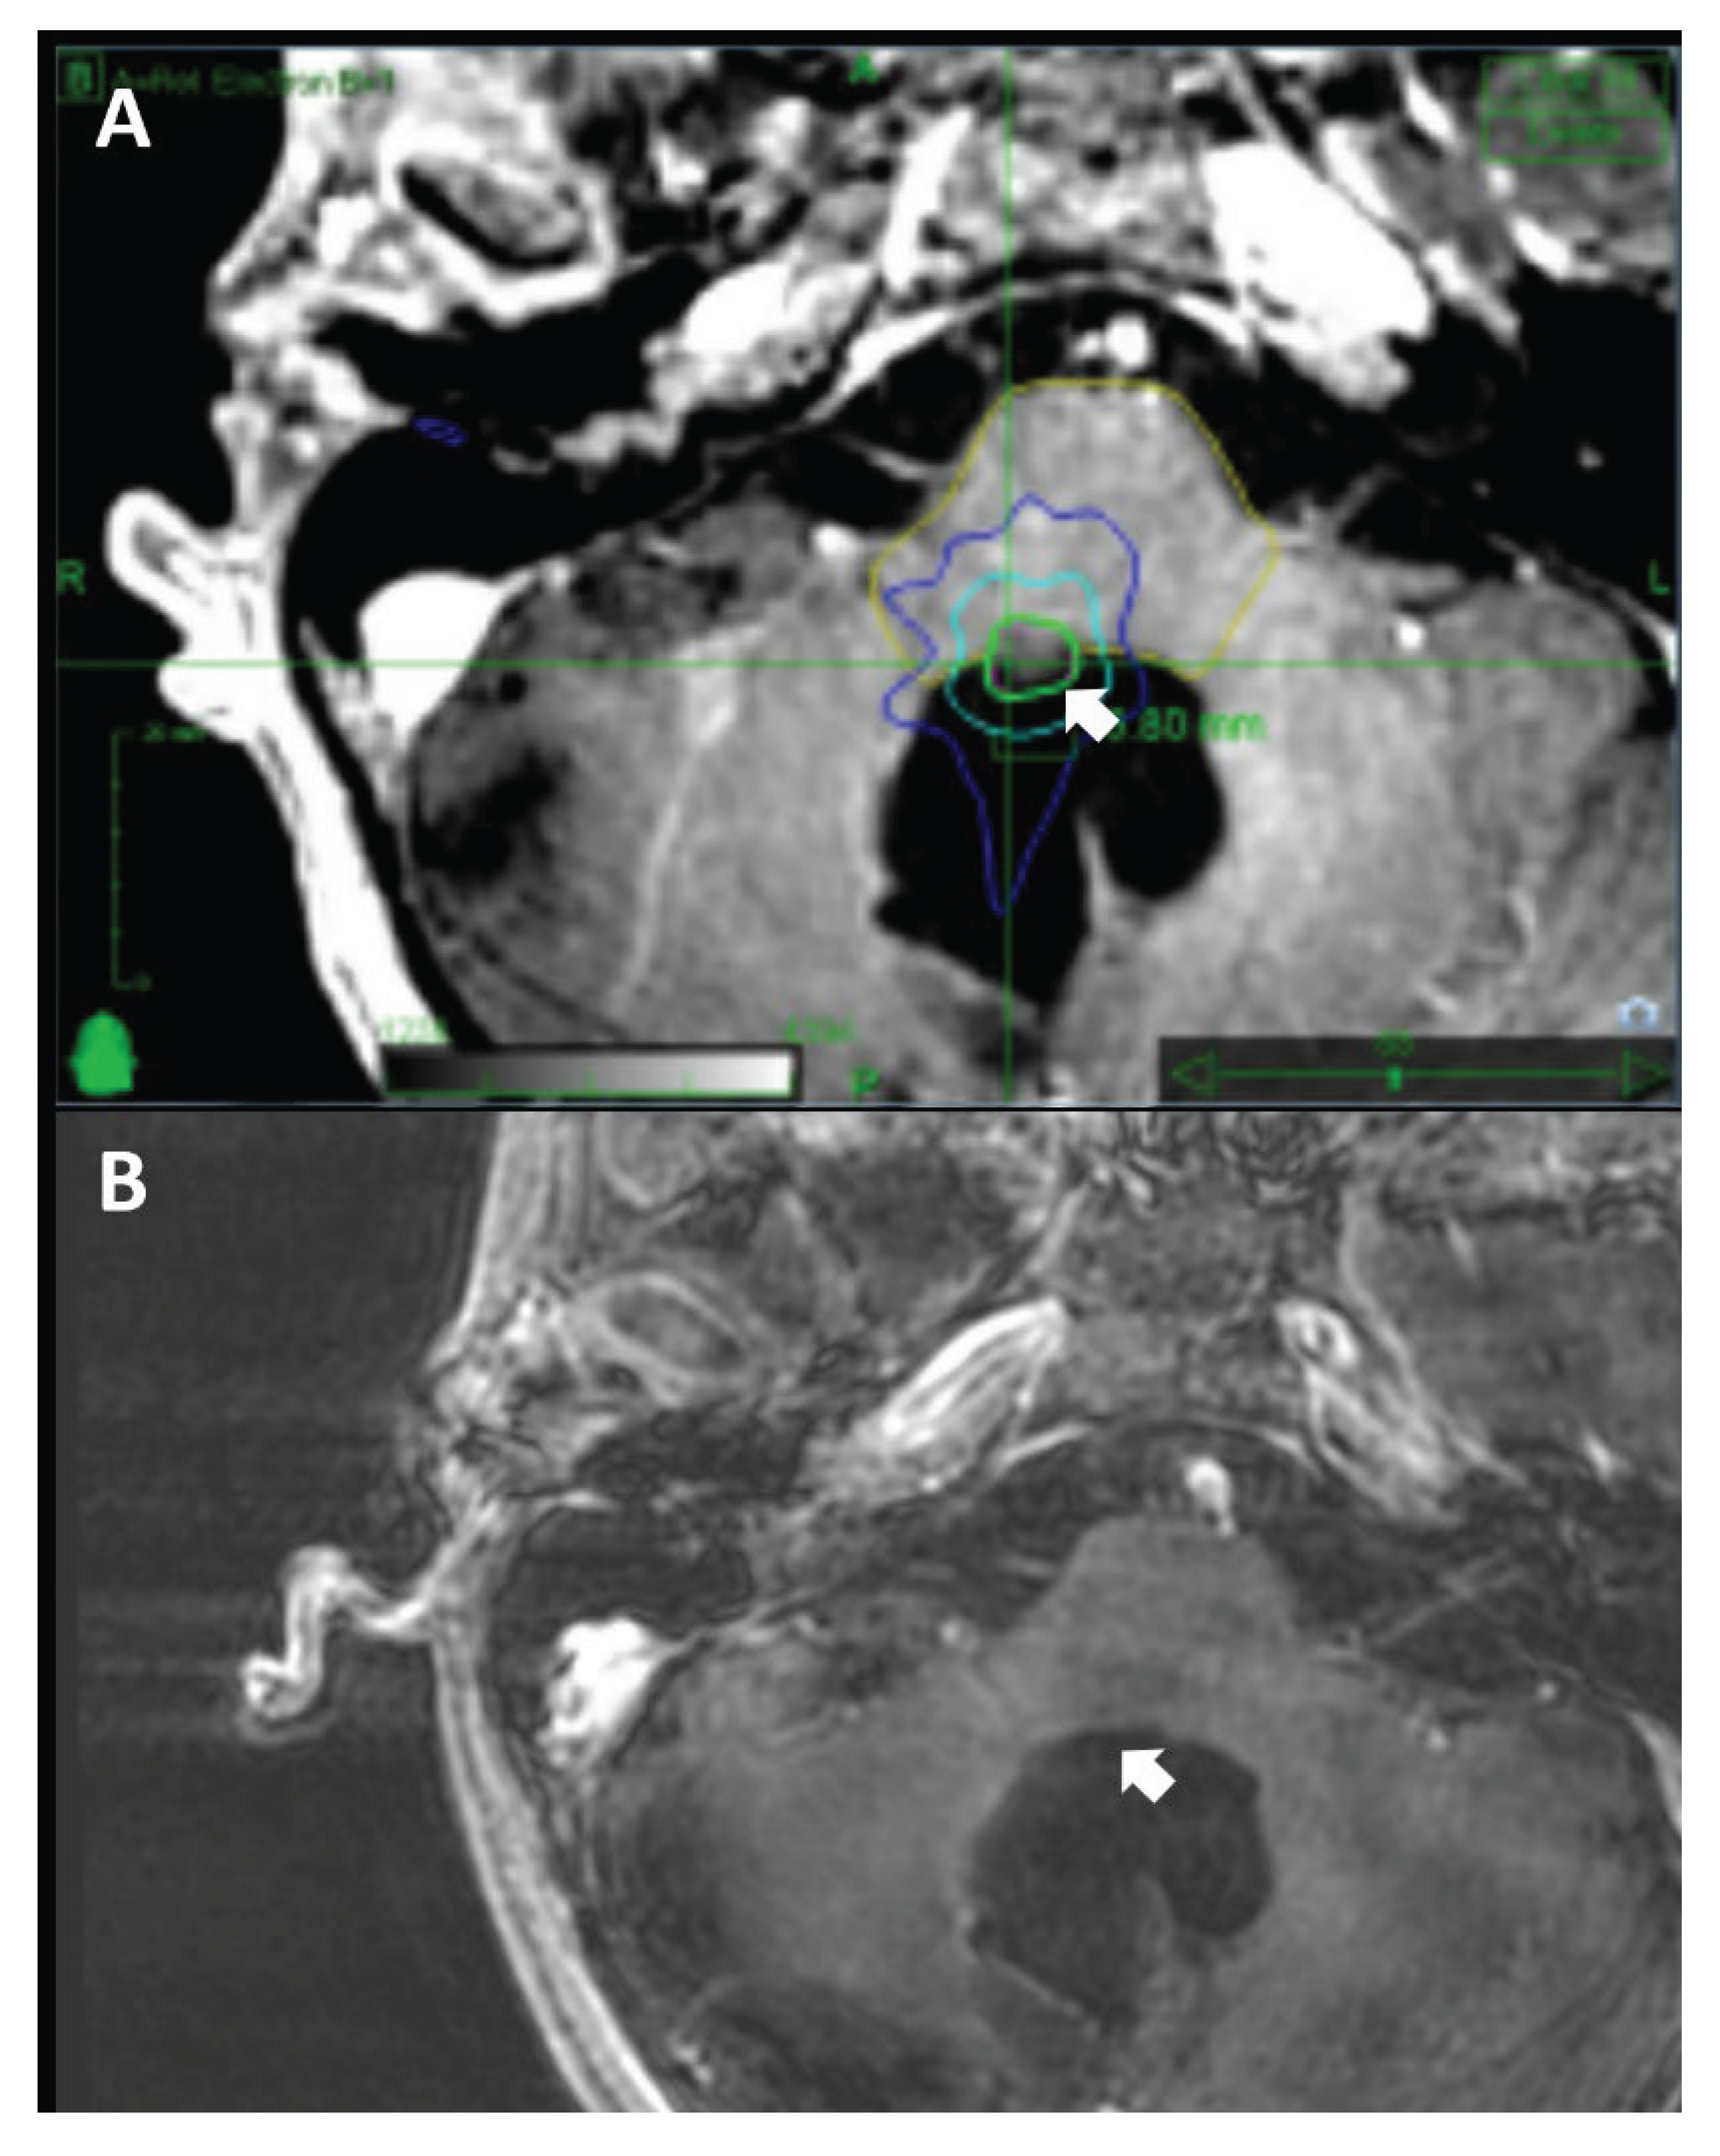

Figure 2. Comparison of A. a baseline CyberKnife treatment plan and B. the most recent radiographic follow-up evaluation of a 11-year-old male patient with a cervicomedullary recurrent medulloblastoma status post surgical resection and adjuvant radiation therapy. A marginal dose of 18 Gy was delivered with the maximum dose of 24.16 Gy in a single fraction to 75% of the isodose line (A). A substantial reduction in tumor size was evident in the 41-month follow-up MRI (B).